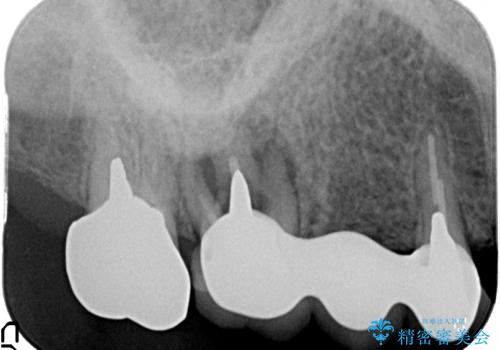

- 「噛むと歯に痛みを感じる、噛めない。」、と痛みの改善を希望され来院されました。

X線写真検査を行ったところ、ブリッジ支台の歯が破折(割れている状態)し抜歯が必要な状態です。

抜歯をしたのちしっかりと咬合力を回復し前後の歯を守るためにも、入れ歯やブリッジではなくインプラントによる咬合機能回復を計画します。